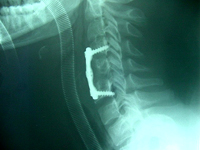

¿Cómo se tratan?

El tipo de tratamiento más indicado para cada lesión dependerá, esencialmente, del tipo de fractura y de la presencia de lesión neurológica. Otros factores a tener en cuenta son la edad y las expectativas del paciente. El tratamiento conservador, habitualmente, consiste en colocar un corsé rígido (de yeso o de plástico) durante unos tres meses. El tratamiento quirúrgico se basa en practicar una fijación interna intentando corregir la vértebra deformada y obtener una estabilización sólida.